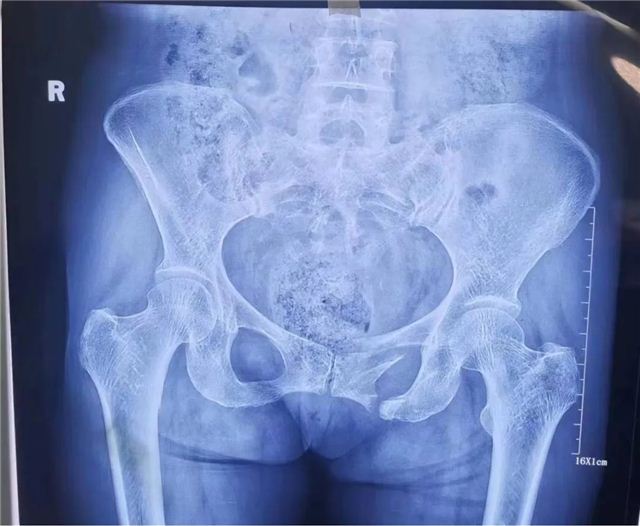

近日,长治二院创伤骨科二病区在智能骨科手术机器人辅助下,成功为两位骶骨、耻骨骨折患者实施手术。 病 例 一 术前影像 入院后,李黎明主任团队综合评估病情,为充分减少创伤,更加利于患者术后康复,决定应用更加先进、更加精准的骨科手术机器人辅助下的微创技术,为徐某行机器人辅助下骨盆骨折闭合复位内固定术。 手术过程中,李黎明主任,徐彦芳医生通过调整透视定位后将骨盆透视影像导入机器人操作界面,在该界面,根据扫描影像规划骶髂螺钉置入位置、方向、长度等数值,在导航系统引导下,经皮小切口精准置入S1,S2通道螺纹导针。经C型臂透视后证实骨折复位满意,导针位置好后,拧入规划长度的螺钉。 术后影像 病例二 术前影像 术后影像 骨科创伤二病区李黎明主任表示,智能骨科手术机器人集合了人工智能、精准手术、安全微创等特色,优势明显。特别是遇到复杂疑难的手术时,利用影像学精准建模,经过术前规划确定骨折位置,明确置入位置和角度,在术中利用灵活的机械臂进行实时定位图像导航,确保螺钉的实际置入零误差,大大降低了术中的风险。 据了解,自2021年10月“天玑”骨科手术机器人投入使用以来,我院骨科共为76名,骨折、骨伤患者成功实施了手术。